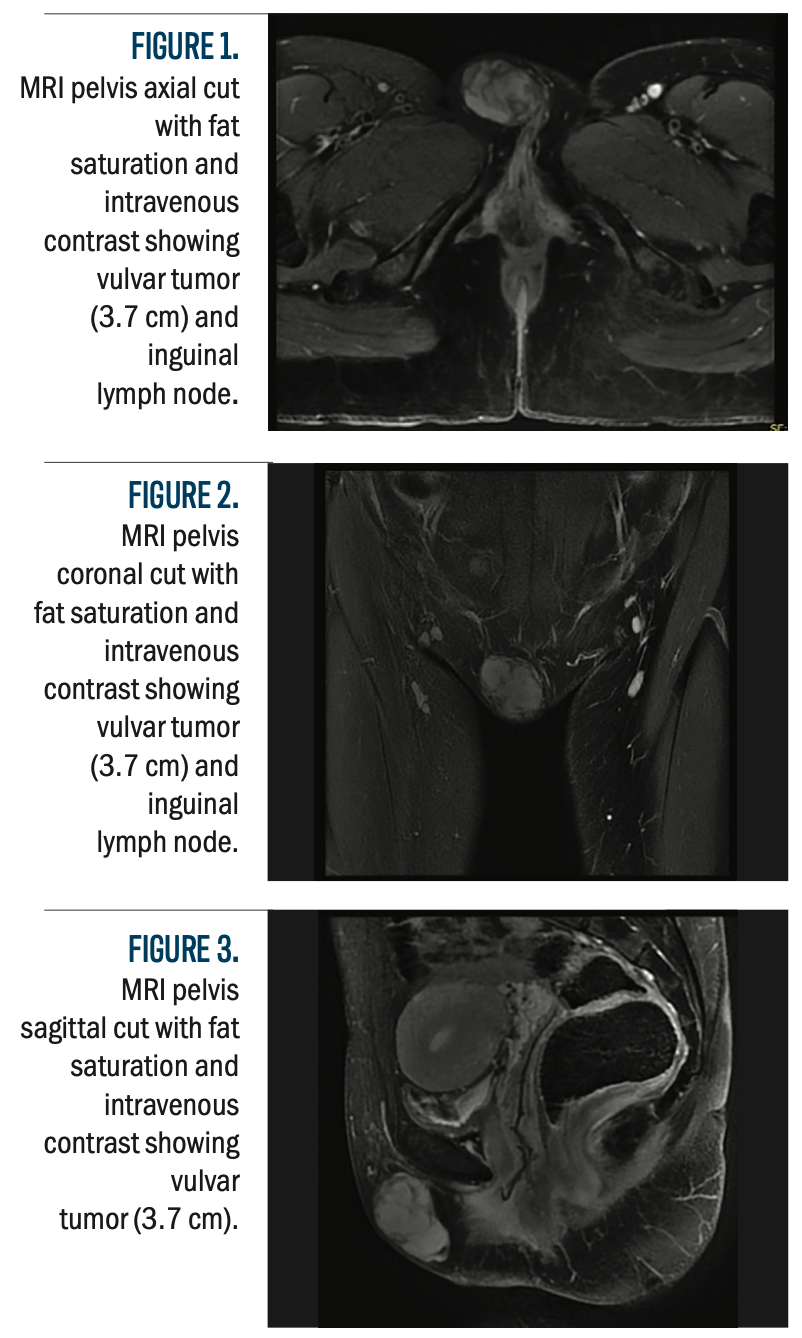

MRI disclosed a 3.7-cm well-circumscribed subcutaneous mass in the right labia majora, having no aggressive hallmarks or related adenopathy, as shown in Figures 1 to 3. After imaging and histopathological confirmation of PES, the patient received treatment that involved surgical excision and adjuvant radiotherapy. The differential diagnosis consisted of superficial angiomyxoma, with less probable chances of angiomyofibroblastoma or myxoid leiomyoma; however, sarcoma was not be conclusively removed.

Figures 1-3.